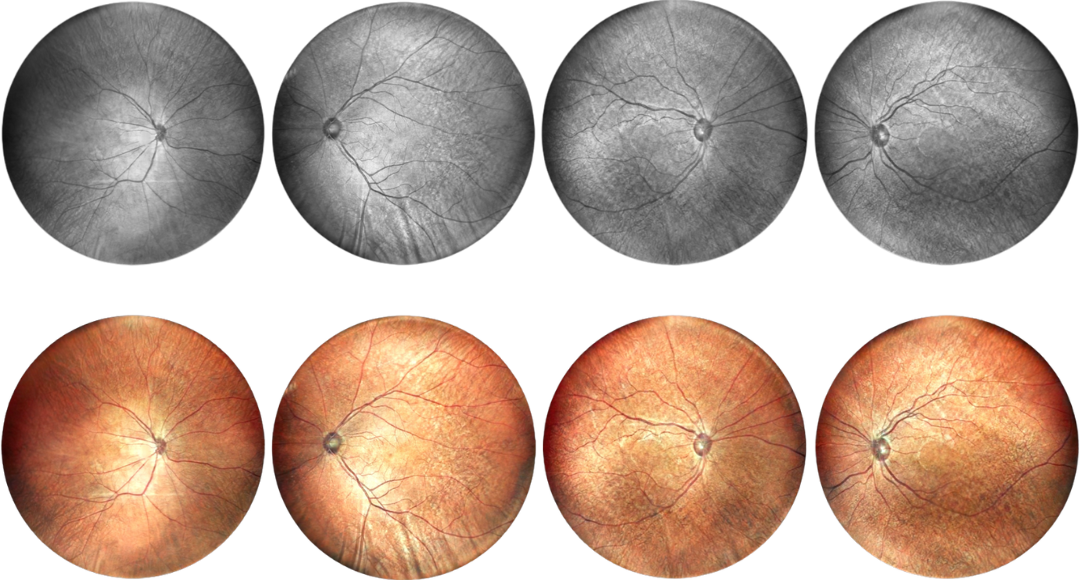

Multi-wavelengh Laser Imaging

Single Infrared Laser

Infrared laser wavelength 840 for retina imaging at 130 degrees

Double Lasers

Infrared laser 840 wavelength and 520 green laser for retina and choroid imaging at 130 degrees

Four Lasers

Infrared laser and green+red+blue laser for retina and choroid imaging at 130 degrees

Fundus Cases Display

Our SLO makes fundus examination easier for you, capturing ultra-clear and wide-angle images of the retina and choroid, and then synthesizing color fundus images to present a rich picture of the fundus status.